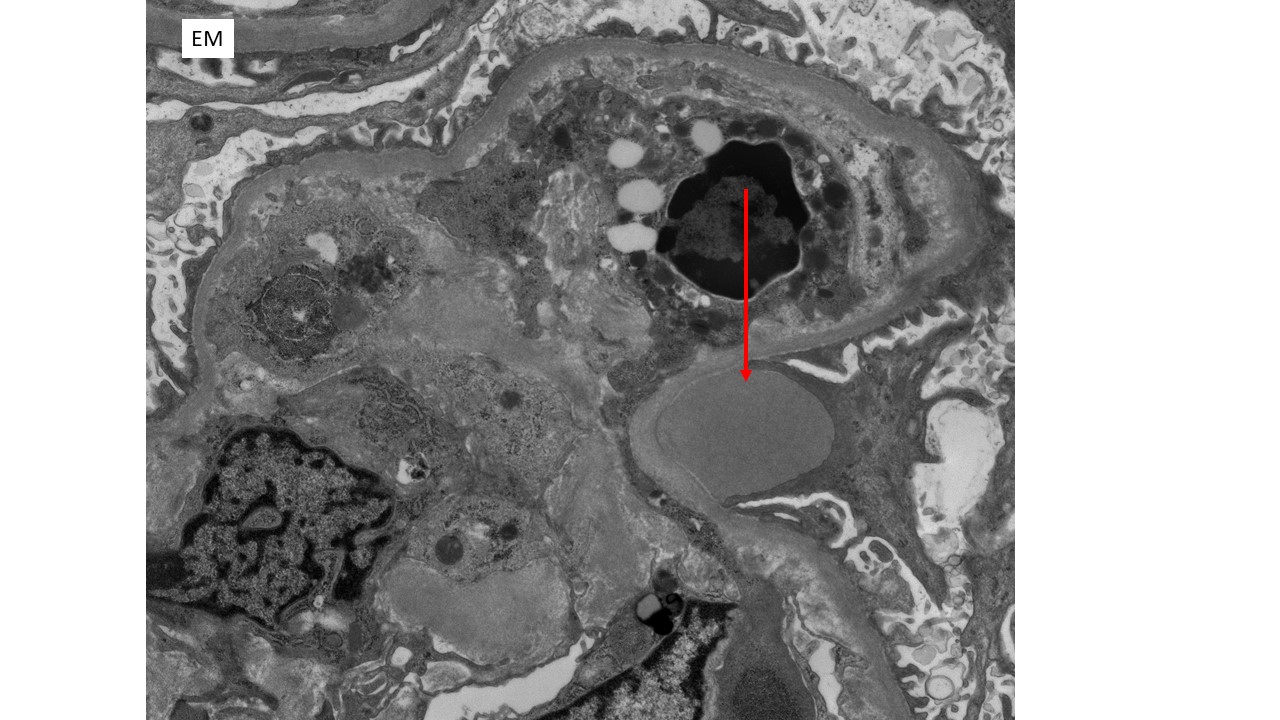

The findings in this patient’s renal biopsy are characteristic of acute postinfectious glomerulonephritis. Light microscopy shows a diffuse and global glomerular exudative process. Glomerular hypercellularity is primarily due to an influx of leukocytes (especially neutrophils, but also admixed monocytes), but which also includes a component of intrinsic renal cell proliferation (e.g. podocytes and mesangial cells), as well as endothelial cell swelling. Jones silver stain highlights the capillary basement membranes within glomerular tufts, and leukocytes and swollen endothelial cells can be seen filling and distend the glomerular capillary lumina. Immunofluorescence staining in this case showed predominant staining for C3 (3+ intensity), with lesser staining for IgG (1+ intensity) in a coarse chunky granular pattern that is mainly seen along capillary walls, often described as “lumpy bumpy” or “starry sky”, indicating a predominantly subepithelial deposition of immunoreactants. Other immunoreactants were negative. Electron microscopy in this case was classic of postinfectious glomerulonephritis, with large “hump-like” electron dense deposits seen in the subepithelial location.